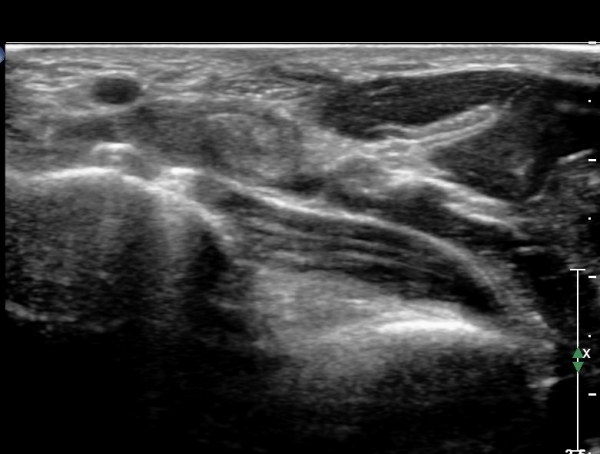

¾Æ·§ÆÈ ÇϺκΠȾ´Ü¸é°Ë»ç¿¡¼­ Àü°ñ°£ ½Å°æ Áö¹è¸¦ ¹Þ´Â  PQ ¿¡¼­ ½Å°æ¸¶ºñ ¼Ò°ß(°í¿¡ÄÚ ±ÙÀ§Ãà)À»

º¸ÀÌÁö ¾ÊÀ¸³ª  FPL ÈûÁÙÀÇ Àú¿¡ÄÚ ºÎÁ¾ÀÌ °üÂûµÇ°í(»çÁø 2, 3) ³»°íÁ¤¹°ÀÌ FPL °ú Á¢ÃËÇϰí ÀÖÀ½ÀÌ °üÂûµÊ(»çÁø 3)

ŽÃËÀÚ¸¦ Á¶±Ý ¸»´ÜÀ¸·Î À̵¿ÇÏ´Ï FPL Å©±â°¡ ±Þ°ÝÈ÷ °¨¼ÒÇÔ. FCR,  FDP ÁÖº¯ ¹Ì¼¼ÇÑ ¼ö¾×Àú·ù °üÂûµÊ(»çÁø4, 5)

ŽÃËÀÚ¸¦ Á¶±Ý ´õ ¸»´ÜÀ¸·Î À̵¿ÇÏ´Ï FCR¿Í FDP »çÀÌ¿¡¼­ Àú¿¡ÄÚ »óÅÂÀÇ FPL °¡ °üÂûµÇ°í °íÁ¤¹°¿¡ ÀÇÇÑ

¾Ð¹ÚÀÌ °üÂûµÊ(»çÁø 6, 7)